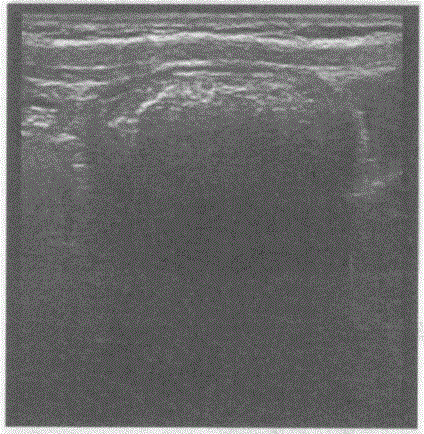

临床资料:女,56岁,自述1周前进食柿子后便秘。超声综合描述:上腹部可见弧形强回声光带,后伴声影,动态观察内未见蠕动。超声提示:A.肠结石...

问题 临床资料:女,56岁,自述1周前进食柿子后便秘。 超声综合描述:上腹部可见弧形强回声光带,后伴声影,动态观察内未见蠕动。 超声提示:

选项 A.肠结石 B.平滑肌肉瘤 C.肠套叠 D.腹腔肿大淋巴结

答案 A